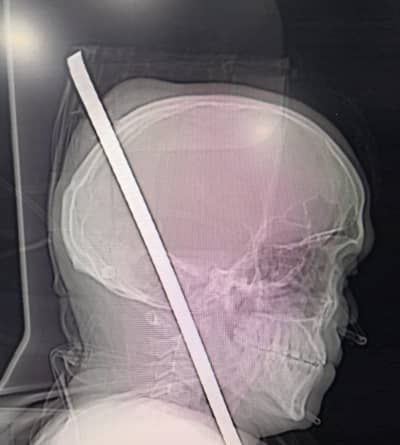

आनंद पांडे, टीव्ही 9 मराठी, मुंबई : देव तारी त्याला कोण मारी, या म्हणीचा प्रत्यय मुंबईतील चेंबूर परिसरात बघायला मिळाला. उंच इमारतीच्या 13 व्या मजल्यावरुन पडलेल्या मजुरावर डॉक्टरांनी गुंतागुंतीची यशस्वी शस्त्रक्रिया केली. महत्त्वाचं म्हणजे या मजुराच्या छातीत सळई घुसून ती जबड्यावाटे डोक्यातून कवटी फोडून बाहेर आली होती. मात्र चेंबूर येथील झेन मल्टीस्पेशॅलिटी रुग्णालयातील डॉक्टरांनी जबरदस्त कामगिरी करुन, 24 वर्षीय कामगाराचा जीव वाचवला.

राकेश जाधव हा 24 वर्षीय कामगार चेंबूरमधील बांधकाम सुरु असलेल्या इमारतीमध्ये मजुरीचं काम करत होता. त्यावेळी तोल गेल्यामुळे तो 13 व्या मजल्यावरुन खाली कोसळला. खाली बांधकाम साहित्य असल्यामुळे लोखंडी रॉड थेट त्याच्या छातीत घुसला. छातीतून हा रॉड वर जबड्यात आणि तिथून डोक्याच्या कवटीतून बाहेर आला. मंगळवारी 20 नोव्हेंबरला ही घटना घडली. त्यावेळी सहकाऱ्यांनी राकेशला तातडीने चेंबूर येथील झेन रुग्णालयात दाखल केलं.

यावेळी डॉक्टरांसमोर त्याच्या डोक्यात घुसलेली सळई काढण्याचं मोठं आव्हान होतं. कारण ती सळई राकेशच्या छातीतून जबड्यावाटे कवटी फोडत डोक्यातून बाहेर आली. त्यामुळे ऑपरेशन नेमकं करायचं कसं, असा प्रश्न डॉक्टरांसमोर होता. डॉक्टरांनी ही गुंतागुंतीची शस्त्रक्रिया केली. तब्बल 5 तास ही शस्त्रक्रिया सुरु होती. डॉक्टरांच्या टीमने घेतलेल्या अथक परिश्रमानंतर अखेर राकेशला वाचविण्यात यश आले.

“मेंदूला रक्तपुरवठा करणाऱ्या वाहिनीला गंभीर दुखापत झाल्याने ही शस्त्रक्रीया अतिशय आव्हानात्मक ठरली. अशा प्रकरणांत रुग्णाचा मृत्यू होण्याची शक्यता नाकारता येत नाही”, असे झेन रुग्णालयाचे संचालक डॉ. रॉय पाटणकर यांनी सांगितले.

डॉ. बटुक डिओरा, डॉ. प्रमोद मस्जीद, डॉ. प्रमोद काळे तसेच त्यांच्या टीमने ही शस्त्रक्रिया केली.